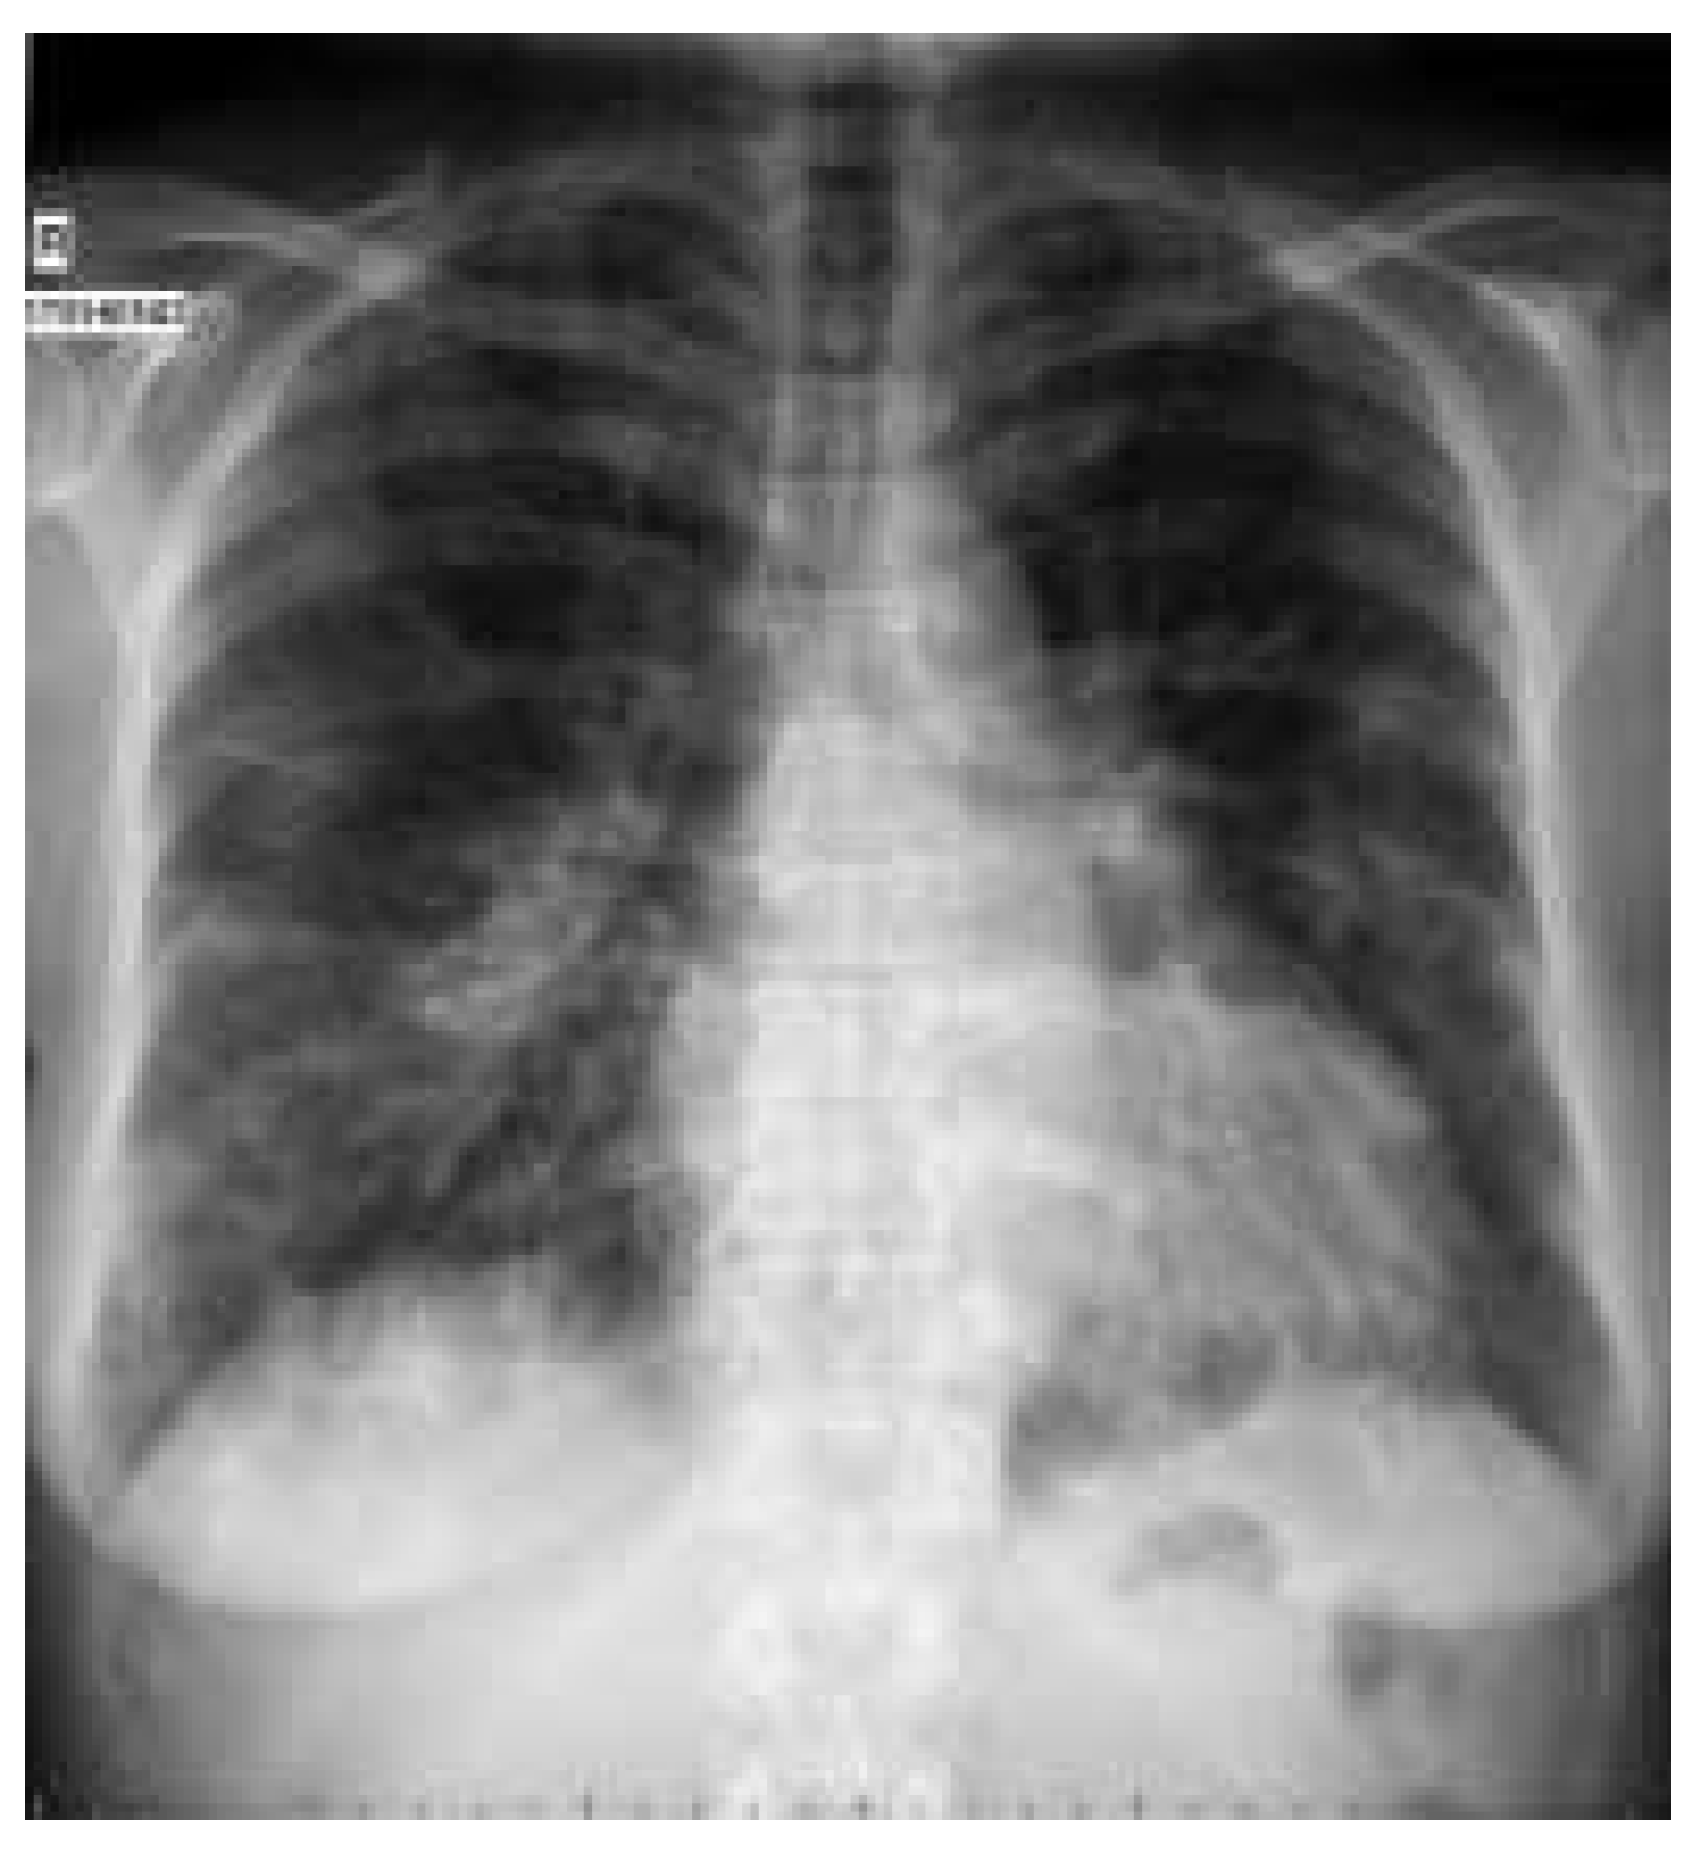

Die arterielle Blutgasanalyse zeigte eine Hypox mie (pO2 3,7 kPa; SO2 64%) trotz Hyperventilation (pCO2 3,7 kPa; pH 7,53). Die BSR betrug 81 mm/h, das CRP 391 mg/l. Die Leukozytose von 17,6109/l war ohne Linksverschiebung. Der INR betrug 5,4. Kreatininkinase und Troponin waren normal. Hingegen waren die LDH auf 777 U/l (normal 240 480) und die alkalische Phosphatase auf 241 U/l (normal 42 98) erh ht. Der Digoxin-Spiegel lag mit 2,7 nmol/l etwas ber dem therapeutischen Bereich (1 2,6), der Desethylamiodarone-Spiegel mit 1,6 mmol/l im Normbereich (0,6 3,0). Drei Blutkulturen blieben ohne Wachstum, das Sputum war ohne relevanten pathologischen Befund. Legionellen und Pneumocystis carinii wurden ausgeschlossen. Das Thorax-R ntgenbild zeigt schwere interstitielle Ver nderungen (Abb. 1).

Abbildung 1. Thorax-Röntgenbild bei Eintritt: schwere interstitielle Veränderungen.